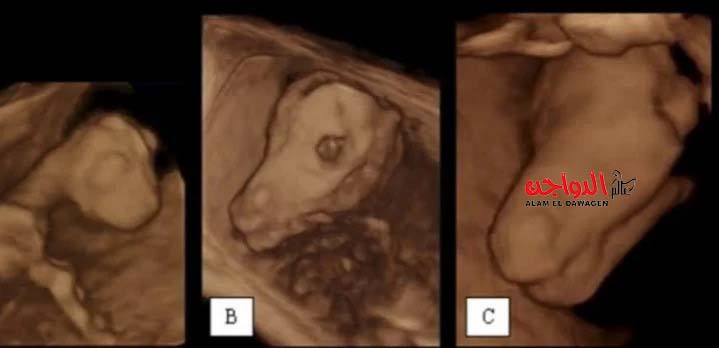

لم تعد اشعة السونار قاصرا على إجراءات الكشف عن الحمل عند الحيوانات، حيث أكد عددا من الأطباء البيطريين، باعتبار اشعة السونار وسيلة أكثر أمانا من الجس أو تلك الطرق التقليدية للتعرف على الأجنة، لكنه أصبح الآن أكثر تطورا، حتى يمكن القول أنه ساهم فى الحفاظ على رؤوس ماشية من الثروة الحيوانية، ووفر وسائل أكثر راحة وعناية للحيوانات لتحديده المشكلات التي يعانوا منها بشكل أكثر دقة.

يقول الدكتور وليد عادل أبو عامر، أخصائى الأشعة التشخيصية البيطرية، إن السونار البيطرى بدأ استخدامه فى مصر منذ عام 1989، لكنه كان قاصر في ذلك الوقت على الكشف عن وجود حمل من عدمه، لكن بتقدم الوقت والدراسات أصبح حاليا الجهاز يمكنه حساب عمر الجنين باليوم، مشيرا إلى أن كثيرا من أساتذة المعاهد البحثية والجامعات المصرية أسسوا لهذا العلم، حتى أن السونار البيطرى أصبح يمكن من خلاله عمل فحص باطنة كامل للحيوان، وذلك رغم تعدد وسائل التشخيص البيطرى، مثل: الإكس راى، المناظير البيطرية، والسى بى سى، وغيرهم، إلا أن جهاز السونار هو الأكثر استخداما والأشمل، ويمكن للأطباء البيطريين الاعتماد عليه والاستغناء عن كثيرا من الأجهزة.

واشار أبو عامر، أن السونار يُستخدم مع حيوانات المزرعة "البقر، الجاموس، الجمال"، في العديد من الفحوصات، التقليدي كتحديد الحمل، والحديث في الكشف عن مشكلات الرحم "الالتهابات الرحمية" بدرجاتها الثلاثة، أو صديد الرحم والذى في حال إجراء الكشف بطريقة "الجس التقليدية" قد يُفسره الطبيب البيطرى على أنه حمل، إلا أن السونار يُحدد المشكلة بدقة وبالتالي يوفر جُهد وتكلفة كبيرة جدا يدفعها مالك الحيوان فى طرق الكشف القديمة التي قد لا تُصل الطبيب إلى المرض الذى يعانى منه الحيوان سريعا.

وعدد الأمراض التي يمكن اكتشافها من خلال الكشف بالسونار، حيث يمكن الوقوف على أمراض تناسلية حيوانات المزرعة، والتي من بينها: أمراض المبيض "التحوصل، أو جسم أصفر ثابت"، لافتا إلى أن هذه الأمراض كان يتم التعامل معها قبل بحقن الحيوان بحقنة بتكلفة كبيرة، وفى حال عدم وجود نتيجة يتم الحقن مرة أخرى، أما اليوم فكشف واحد بالسونار يتم تحديد المشكلة ومنح العلاج الملائم لها في مرة واحدة، مضيفا: وفى كشف الباطنة لحيوانات المزرعة،: يساهم في اكتشاف العديد من الأمراض مثل: خراج في الكبد، مشكلات الرئتين، والالتهابات الرئوية بأنواعها، واكتشاف مشكلات القلب، مثل: إلتهاب القلب، والذى قد يكون ناتج عن ابتلاع الحيوان لمسمار والذى قد يؤدى إلى نفوق الحيوان، إلا أن السونار يكتشف هذا مبكرا ويتيح الفرصة لإجراء تدخلات جراحية وبالتالي إنقاذ حياة الحيوان.